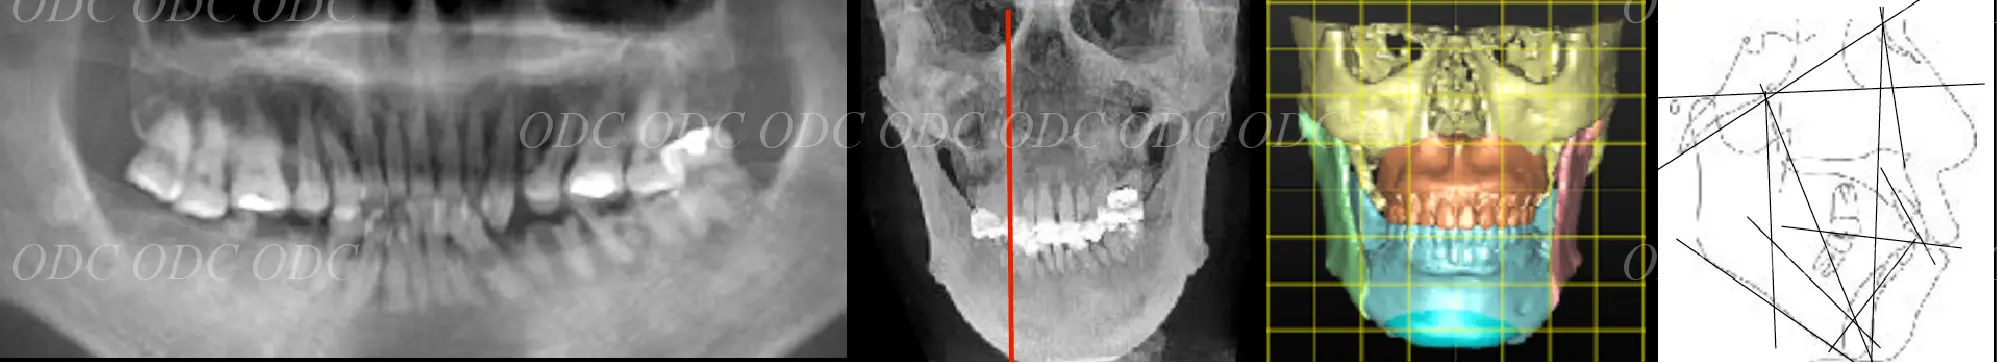

顎変形症

骨格について

骨格のバランスが良ければ機能的にも安定して、口元・顔貌が美しくなります。

左上図は受け口(下顎前突)の骨格(クラスⅢ)。

骨切り手術により下図のような上下顎がバランスのいい状態へ変化させることができます。

左上左図は受け口の逆で下顎が小さい骨格(クラスⅡ)。

SSROという骨切り手術によって上下顎のバランスを良くすることができます。

上顎骨が斜めに傾いてる症例も問題があります。

ルフォーという骨切り手術でゆがみを治すことができます。

上顎骨にルフォー、下顎にSSROを行ったイメージ図です。

骨格に問題があり、骨切り手術を行った方々の口元の変化です。

(左からクラスⅢ、クラスⅡ、上顎骨のゆがみ)

※白線4本、上からフランクフルト平面、口蓋平面、咬合平面、下顎下縁平面

鷹木歯科からご提供いただいた、理想的な骨格の方の顔貌(横顔)と骨格のレントゲン写真です。

理想的な骨格の方は、口腔内が安定しやすくなっています。

噛み合わせを安定するために、当院ではタカギインデックスを用いて咬合平面を設定しております。

アーネット分析

骨格的な問題を抽出するために、顔貌からアーネット分析を行い、上顎と下顎の骨格的な問題を予想いたします。

横顔の写真と骨格的な問題を検討し、治療終了時にどのような横顔になるかを予測することができます。